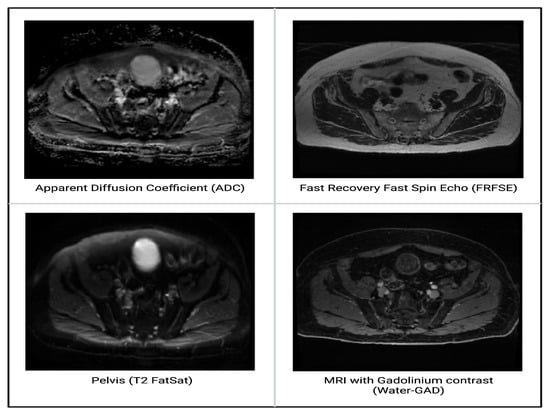

4.1. Signal Weighting

4.1.1. ADC

4.1.2. FRFSE

4.1.3. T2 FatSat

4.1.4. Water-GAD